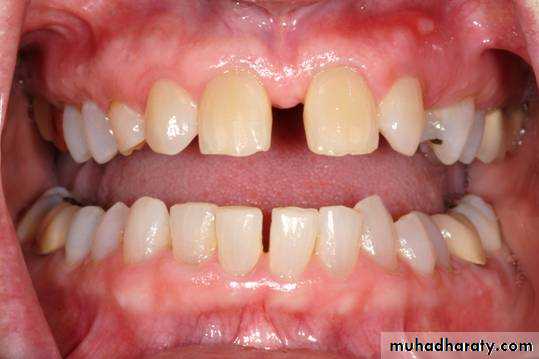

MIDLINE DIASTEMA

DEFINATION OF DIASTEMAA space between adjacent teeth is called a diastema.

DEFINATION OF MIDLINE DIASTEMAMidline diastema refers to anterior midline spacing between the two central incisors.

Fig: Midline diastema